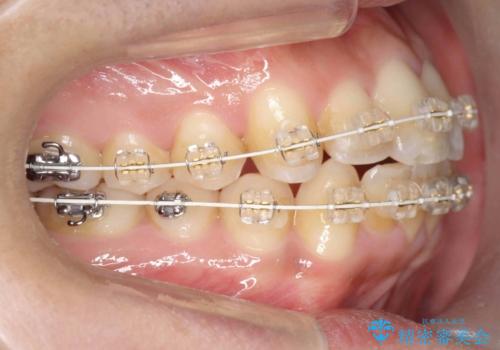

- 矯正装置

- 審美装置

- 治療期間

- 1年6ヶ月

- 治療回数

- 10-30回